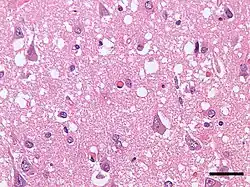

| Micrograph showing spongiform degeneration (vacuoles that appear as holes in tissue sections) in the cerebral cortex of a patient who had died of Creutzfeldt–Jakob disease. H&E stain, scale bar = 30 microns (0.03 mm). | |

Prion diseases are marked by mental and physical deterioration that worsens over time.[5][6] A defining pathologic characteristic of prion diseases is the appearance of small vacuoles in the various parts of the central nervous system that create a sponge-like appearance when brain tissue obtained at autopsy is examined under a microscope.[2][3] Other changes in affected regions include the buildup of PrPSc, gliosis, and the loss of neurons.[7]

The degenerative tissue damage caused by prion disease in the nervous system is characterised by four features: spongiform change (the presence of many small vacuoles), the death of neurons, astrocytosis (abnormal increase in the number of astrocytes), and deposits of abnormal PrP (some of which have the characteristics of amyloid).[22] These neuropathological features have formed the basis of the histological diagnosis of prion diseases for many years, although it has been recognized that these changes are highly variable both from case to case and within the central nervous system in individual cases.[23][22] In humans, prion diseases with different genetic or infectious causes often have different patterns of pathology. For instance, amyloid plaques are rare in most prion diseases, but they are common in some diseases such as kuru and variant CJD. Owing to the rarity of amyloid per se in prion diseases, it is thought that non-amyloid forms of PrPSc are responsible for neurodegeneration.[22] In rare instances of human prion disease, tauopathy resembling the neurofibrillary tangles in Alzheimer's disease is present, highlighting the many ways in which the pathology of prion diseases can vary.[22] Despite this variation, all prion diseases have in common the buildup of abnormal PrP in the nervous system.